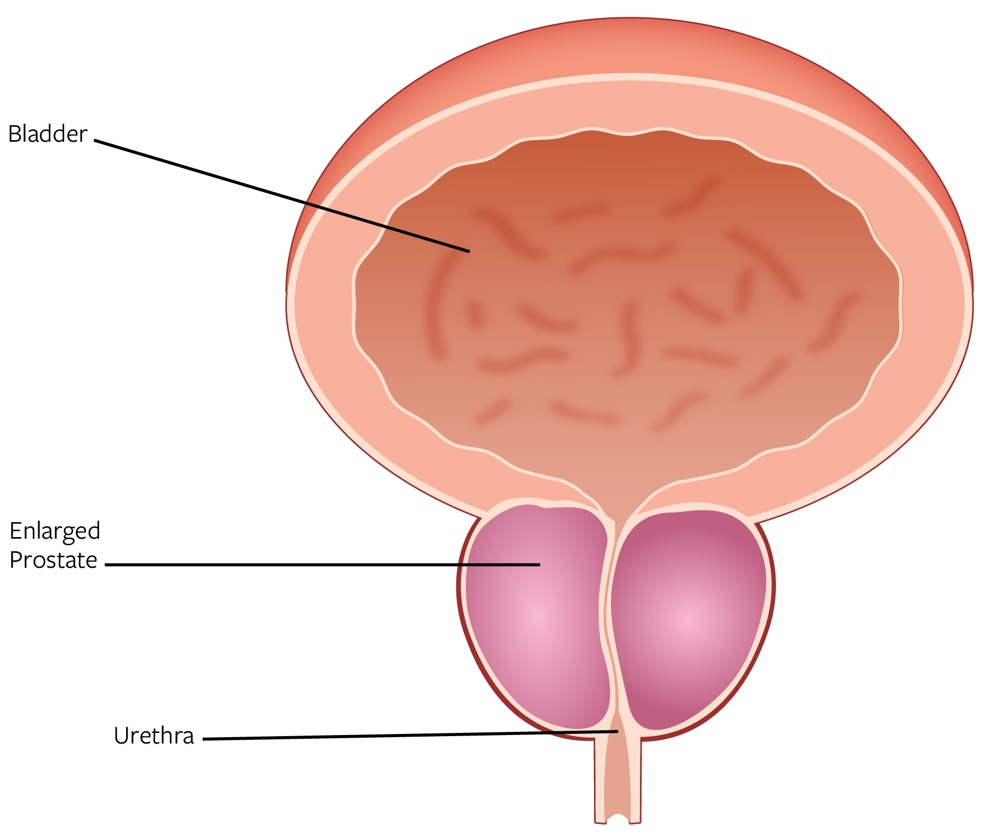

BPH Disease Overview and Diagnosis

BPH refers to the non-malignant enlargement of the prostate gland. As the prostate enlarges, the gland presses against the urethra, which may obstruct or restrict the flow of urine from the bladder and result in uncomfortable LUTS, such as urgency, frequency, urinary retention, straining to urinate and a weak urinary stream. Without treatment, prolonged obstruction may eventually lead to acute urinary retention, urinary tract infections or renal insufficiency. An enlarged prostate can range between roughly 30 ml to above 300 ml. As prostates increase in size so does the complexity of shape where the obstructive tissue will grow back into the bladder (called an intravesical component).

Normal Prostate versus Enlarged Prostate

While some BPH patients are asymptomatic, most will experience symptoms, which generally become more bothersome with age. According to the AUA guidelines, it is estimated that 90% of men between the ages of 45 and 80 will experience LUTS, and 50% of them will experience moderate-to-severe symptoms by the time they are 85 years old, which we believe are predominantly caused by BPH. Furthermore, 50% of men between the ages of 51-60 have pathological BPH. Symptoms associated with BPH can have a significant impact on a patient’s quality of life, including inability to sleep through the night, limiting activities due to proximity to the bathroom, impact on relationships, professional life and social activities, ongoing embarrassment and frustration and impact on sexual function. According to our internal marketing survey, 99% of men diagnosed with BPH say symptoms impact their quality of life.